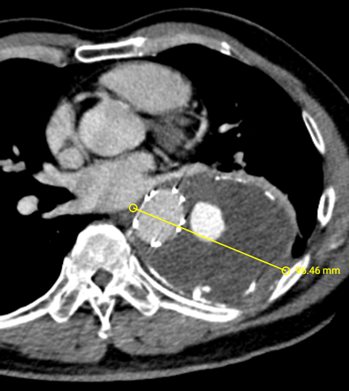

术后8年随访发现假腔明显扩大,最大直径达96mm,伴胸背疼痛,有手术干预指征。

二次手术前CTA